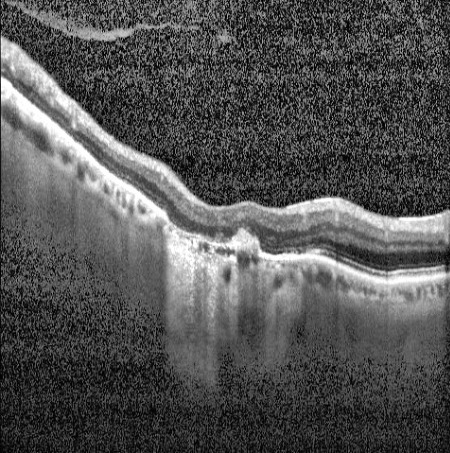

The RetGuard camera captures both fundus photographs and OCT scans — the two gold-standard imaging methods for retinal screening — giving the AI a complete picture of the retina.

Every result comes with visual evidence

RetGuard generates visual heatmaps that highlight the exact retinal regions that influenced each screening result — so clinicians can see what the AI found and where.